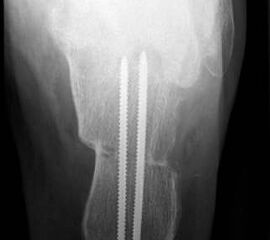

Die lateralisierende Calcaneus-Osteotomie ist ein Standard-Operationsschritt bei fast jeder Hohlfuβkorrektur. Der biomechanische Effekt der Osteotomie ist eine Verschiebung des Fersenkontaktpunktes und damit der beim Rückfuβ varus medialisierten Belastungsachse durch das OSG nach lateral. Diese statische Rückfuβ-Korrektur allein ist in der Lage, den bei Pes cavovarus anteromedial erhöhten OSG-Druck, der sehr wahrscheinlich zur korrespondierenden Arthrose führt, zu neutralisieren 7. Zuklappende Osteotomien mit Entnahme eines lateralen Knochenkeils haben sich dabei weniger effektiv gezeigt als solche mit Lateralisation des Tubers. Mit der Lateralisation des Achilles-Ansatzes verringert sich die Inversionskraft der Sehne zugunsten der schwachen Eversion, wodurch gleichzeitig die Prädisposition für Supinationstraumata reduziert wird. Neben der klassischen Dwyer-Osteotomie (Entnahme eines lateralen, vertikalen Keils 8 haben sich vor allem die technisch einfache Verschiebe-Osteotomien („sliding osteotomy“) und die Z-förmigen Osteotomien (Pisani 1993, Malerba 9) mit Entnahme eines lateralen Keils aus dem horizontalen Anteil der Osteotomie aber ohne Lateralisation des Tuberfragmentes, sowie die Korrektur nach Hintermann (Knupp 2008) mit zusätzlicher Lateralisation des Tuberfragmentes) durchgesetzt. Bei neutral aligniertem OSG ist keine supramalleoläre Tibia-Osteotomie zur Korrektur des Rückfuβ varus indiziert. Generell sollten Osteotomien gegenüber korrigierenden Arthrodesen der Vorzug gegeben werden. Die im Folgenden beschriebene Verschiebeosteotomie ist technisch einfach und hinsichtlich OSG-Druckneutralisation ebenso effektiv wie die Z-Osteotomien 7.

• Definitive Fixation über die dorsoplantare Querinzision mittels Schrauben (normale 3.5 mm Kortikalsischrauben sind hier völlig ausreichend).

• Kontrolle der korrekten Schraubenlage im BV (Abb. 3).